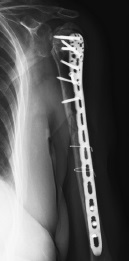

The control X-rays showed a consolidated fracture of the humeral diaphysis 9 months postoperatively, as well as the development of avascular necrosis of the left humeral head, nonunion, and migration of the greater tubercle into the subacromial space (Fig. 4). The shoulder function was limited, and the pain syndrome up to 5 VAS points persisted during movements, as well as a pronounced limitation of the amplitude of active movements with the abduction of up to 70°, flexion of up to 90°, external rotation of up to 0°, and internal rotation at the L5 level. However, the patient was fully adapted to daily activities.

Fig. 4. Shoulder control X-ray after 9 months since surgery: consolidation of the diaphyseal part, nonunion, secondary displacement of the greater tubercle and avascular necrosis of the humeral head

After 20 months, stage 2 of the surgical treatment, including removal of metal fixators and total reverse arthroplasty of the left shoulder, was decided together with the patient due to the persistent pain syndrome. A deltoid-pectoral approach was performed, and the metal fixators were removed. Then, tenotomy of the subscapular muscle tendon and long head biceps tendon was performed, and access to the shoulder joint was provided. The remaining nonviable fragments of the humeral head were removed, cementless metaglene was placed with fixation by three screws, and a 38-mm glenosphere was placed.

A decision was made to install a cemented endoprosthesis stem (size 1, diameter 10) because of the reduced bone quality, thin cortical walls, the risk of low integration, and the risk of endoprosthesis stem instability. The height of the shoulder component was determined by the most intact medial bone edge of the humerus. The 38/+3 cup was installed after fitting. The final radiographs are presented in Figure 5.

Fig. 5. Shoulder X-rays in the early postoperative period after left shoulder arthroplasty: a — Y-shaped view; b — direct view